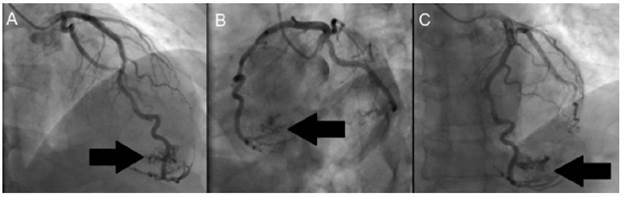

Then, invasive stratification was performed by left ventriculogram and selective coronary angiography (Figure 2 and 3), in which a dominant right coronary system with epicardial coronary arteries, without obstructive lesions and presence of a fistula of the distal anterior descending artery to the left ventricle was found.

Coronary angiography of the left coronary artery.

Figure 3: Coronary angiography of the left coronary artery.

Source: Own elaboration.

Figure 2 shows extravasation of contrast medium into the apical territory irrigated by the anterior descending artery, while, in Figure 3, diagnostic injection on the left coronary artery shows posteroanterior projections (ARC 18°, RAO 25°) (Figure 3A), left oblique with caudal angulation (CAU 20°, LAO 49°) (Figure 3B) and left oblique with skull (CRA 18°, LAO 8°) (Figure 3C). Extravasation of contrast medium is also observed from the anterior descending artery to the left ventricle (black arrow).